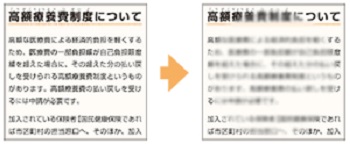

抗VEGF薬治療(硝子体内注射)の眼内注射をおこなう前後の注意点

抗VEGF治療薬を行う前の3日間、行ったあとの3日間は、感染予防のために抗菌点眼薬を患者様ご自身で点眼していただく必要があります。

抗VEGF治療薬を行う前の3日間、行ったあとの3日間は、感染予防のために抗菌点眼薬を患者様ご自身で点眼していただく必要があります。

注射の際には改めて消毒を行いますが、感染リスクをできる限りゼロに近づけるめ、必ず医師の指示通りに点眼を行ってください。